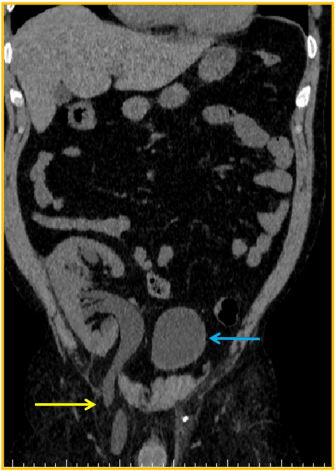

Although there were no other symptoms, a slow increase in serum creatinine, from 1,5mg/dL to 2,4mg/dL, was noticed in the first three post-operative years. Physical examination found a right sided inguinal hernia. Abdominal ultrasound revealed a severe hydronephrosis of the transplant kidney but the ureter could not be visualized. An abdominal computed tomography (CT) showed severe ureterohydronephrosis with herniation of the ureter into the inguinal canal (Figure 1), prompting surgical exploration. Through the previous right-side Gibson incision, the spermatic funiculi and hernial sac were identified and isolated. Exploration of the herniary sac revealed a long ureter, with a dilated proximal portion (3cm wide), followed by an abrupt transition to a rather typical distal segment, close to the bladder wall (Figure 2). Both segments appeared well vascularized and viable. Given these findings and the excessive length of the ureter, ureterectomy of the distal segment followed by a tailored ureteroplasty (Figure 3) and new Lich-Gregoir ureteroneocystostomy of the proximal segment over a double J stent was performed. The posterior wall defect was mended through Lichtenstein technique. A bladder catheter was kept for one week and the ureteral stent for one month. After the removal of the bladder catheter, ultrasound and CT scan were unremarkable (Figure 4) and serum creatinine decreased from 2.4mg/dL to 2.05mg/dL. Patient is still in follow-up, without any sign of recurrence.

Figure 1. CT scan: blue arrow – bladder; yellow arrow – herniated ureter through the inguinal canal

The US mostly reveals severe hydronephrosis and no visualization of ureter´s full length. The CT scan shows the transplanted ureter dilation and the ureteric- inguinal hernia, making it possible to come to the anatomical diagnosis [1,15,18]. There was no explanation for the need of MRI, but one could think that the pelvic area and the inguinal canal anatomical features may become even more striking through these images.